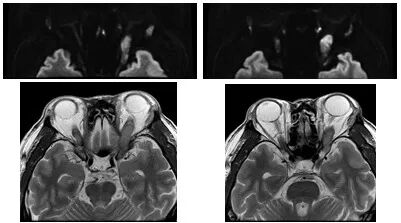

▲ 视神经存在病灶成像对比

视神经存在病灶,靠近富含空气的鼻腔,传统成像方式的磁敏感伪影往往会造成图像严重变形或者信噪比下降;Pioneer 聚焦视神经周围组织,对病灶结构以及与周围组织的关系清晰成像,图像精准无变形,为临床诊断提供了更准确的信息。